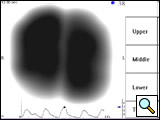

The resulting sound or vibration energy can also be analyzed regionally for upper (top 2 rows of sensors), middle (3 rows of sensors), and lower zones (bottom 2 rows of sensors) for both the right and left lung and presented in a table (Figure 3). Presumably, both the regional quantification of breath sounds and the dynamic image are affected by changes in frequency, intensity, space, and timing of airflow and, therefore, can provide useful clinical information regarding lung condition.

Figure 3: Quantitative assessment of breath sound distribution in the same healthy subject depicted in Figure 2, shown as a table of percentages. Vibration energy is concentrated primarily in the middle and lower regions with less energy in the upper lung fields.